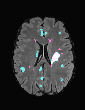

In recent years, data-driven machine learning (ML) methods have revolutionized the computer vision community by providing novel efficient solutions to many unsolved (medical) image analysis problems. However, due to the increasing privacy concerns and data fragmentation on many different sites, existing medical data are not fully utilized, thus limiting the potential of ML. Federated learning (FL) enables multiple parties to collaboratively train a ML model without exchanging local data. However, data heterogeneity (non-IID) among the distributed clients is yet a challenge. To this end, we propose a novel federated method, denoted Federated Disentanglement (FedDis), to disentangle the parameter space into shape and appearance, and only share the shape parameter with the clients. FedDis is based on the assumption that the anatomical structure in brain MRI images is similar across multiple institutions, and sharing the shape knowledge would be beneficial in anomaly detection. In this paper, we leverage healthy brain scans of 623 subjects from multiple sites with real data (OASIS, ADNI) in a privacy-preserving fashion to learn a model of normal anatomy, that allows to segment abnormal structures. We demonstrate a superior performance of FedDis on real pathological databases containing 109 subjects; two publicly available MS Lesions (MSLUB, MSISBI), and an in-house database with MS and Glioblastoma (MSI and GBI). FedDis achieved an average dice performance of 0.38, outperforming the state-of-the-art (SOTA) auto-encoder by 42% and the SOTA federated method by 11%. Further, we illustrate that FedDis learns a shape embedding that is orthogonal to the appearance and consistent under different intensity augmentations.